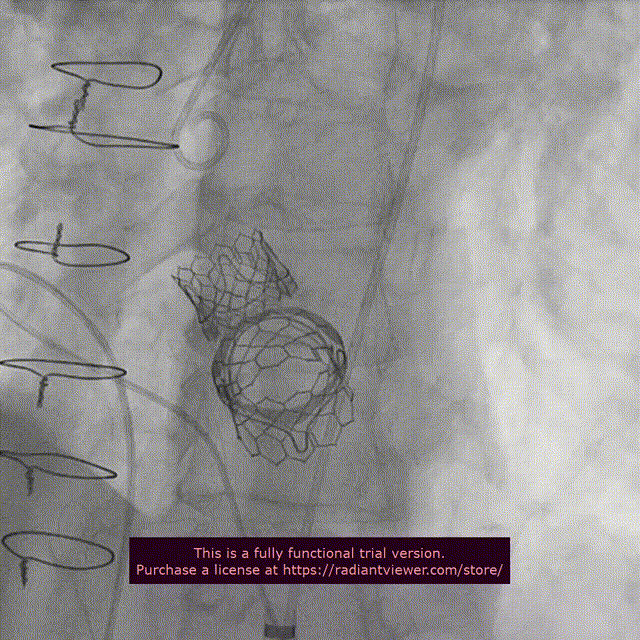

9. 二尖瓣位瓣膜跨瓣、定位、释放

SAPIEN 3瓣膜跨二尖瓣生物瓣

二尖瓣生物瓣位SAPIEN 3瓣膜释放

10. 双瓣植入后左室造影与主动脉根部造影

二尖瓣位SAPIEN 3植入后左室造影

二尖瓣位和主动脉瓣位SAPIEN 3瓣膜功能良好

二尖瓣位SAPIEN 3瓣膜不影响左室流出道